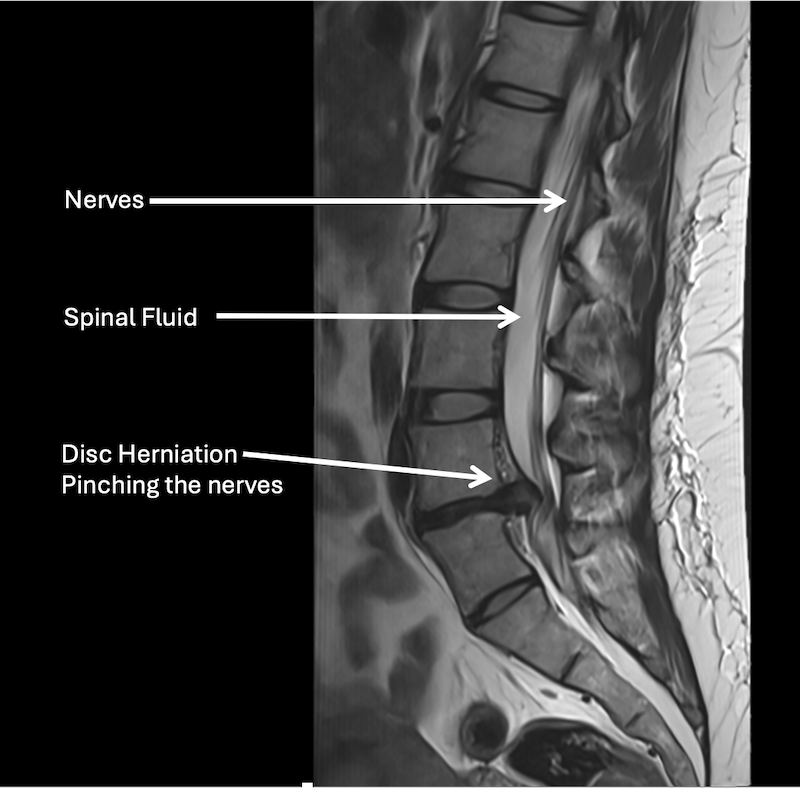

MRI scan of a lumbar spine showing nerve compression from a disc herniation pressing on the nerves, with labels indicating nerves, spinal fluid, and disc herniation pinching the nerves.

MRI helps identify the structure that is compressing the nerve.

MRI helps identify disc herniation and nerve compression.

• X-rays show bones but not discs or nerves.

However, X-rays are also important because they can show your bone alignment and possibly other issues that are not shown on MRI.